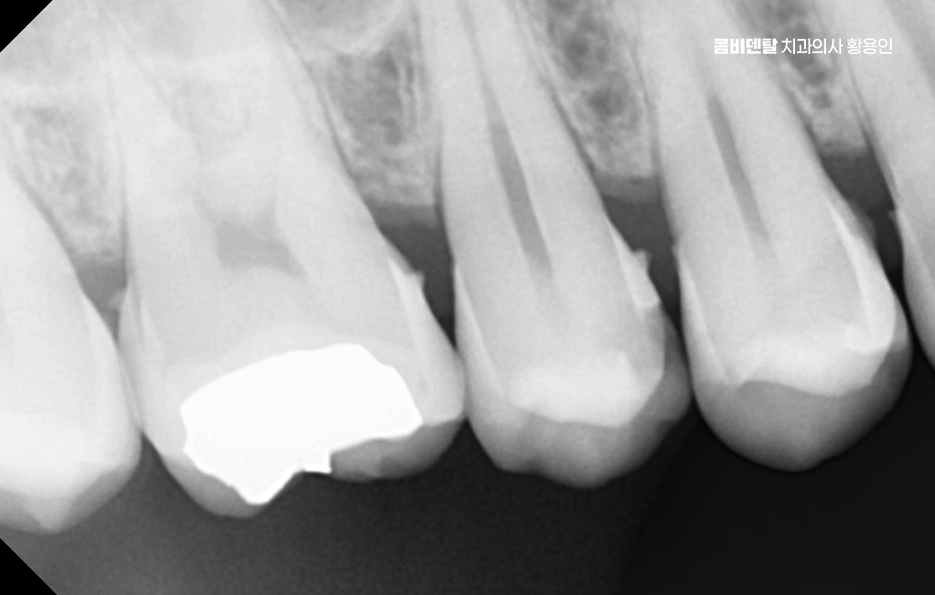

충치 치아 깨짐의 원인부터 살펴보면 대표적인 사례 중 하나는 겉으로 보기에는 작은 충치였던 경우로 치아 표면에 작은 검은 점이 있거나, 음식이 자주 끼는 정도라서 대수롭지 않게 넘겼는데 실제로는 치아 안쪽에서 충치가 넓게 퍼지고 있었던 상황이며 치아는 내부 구조가 약해지면 씹는 힘을 견디지 못하게 되고 그러다 어느 날 딱딱한 음식을 씹는 순간 치아 벽이 무너지듯 깨지는 일이 생길 수 있었어요

특히 어금니에서 이런 일이 자주 발생하는 편으로 어금니는 씹는 힘을 가장 많이 받는 치아인데, 충치가 어금니 씹는 면의 홈을 따라 진행되면 바깥에서는 잘 보이지 않는 경우가 많고 통증도 거의 없어서 치료 시기를 놓치기 쉬울 수 있어요

또 다른 충치 치아 깨짐 대표적인 사례는 오래된 충치 치료 부위에서 치아가 깨지는 경우인데 예전에 레진이나 다른 재료로 충치를 치료했지만, 시간이 지나면서 치아와 재료 사이에 미세한 틈이 생기고 그 안으로 다시 충치가 진행되는 경우가 있어요.

겉으로 보기에는 치료가 잘 된 것처럼 보여서 안심하기 쉬운데 실제로는 보이지 않는 안쪽에서 치아가 계속 썩고 있는 상황일 수 있어서 이런 경우 치아는 이중으로 약해지게 되고, 어느 순간 치료 부위 주변이 함께 깨지면서 문제를 드러내게 되는 거예요.